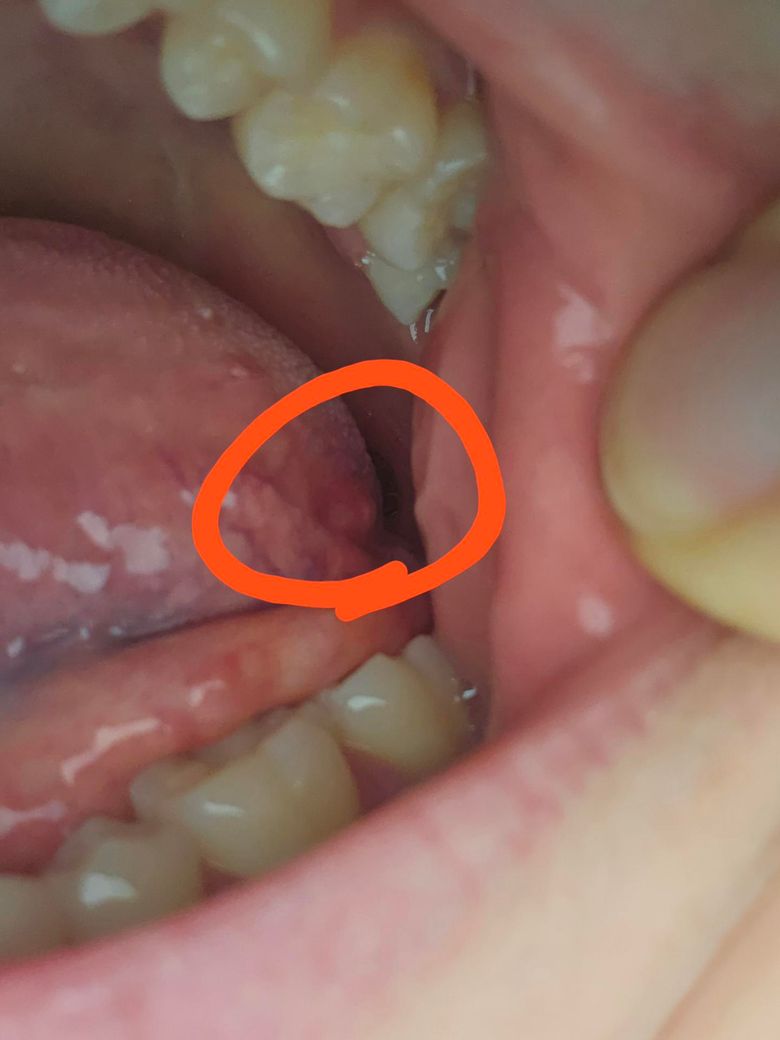

혀 안쪽 엽상유두 쪽 통증이 심한데 왜 그런가요..? (사진)

혀 안쪽 엽상유두 쪽이 빨갛고 통증이 꽤 있는데 무슨 문제가 있는 걸까요.. 이빨에 닿을때마다 깜짝 놀라도록 아프고 평소에도 혀가 움직을 때마다 아프네요..

• 1번 째 사진